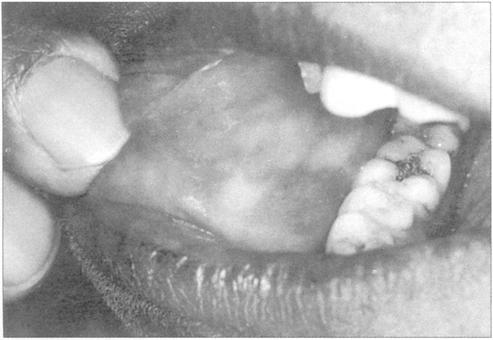

图230 Addison病颊部色素沉着